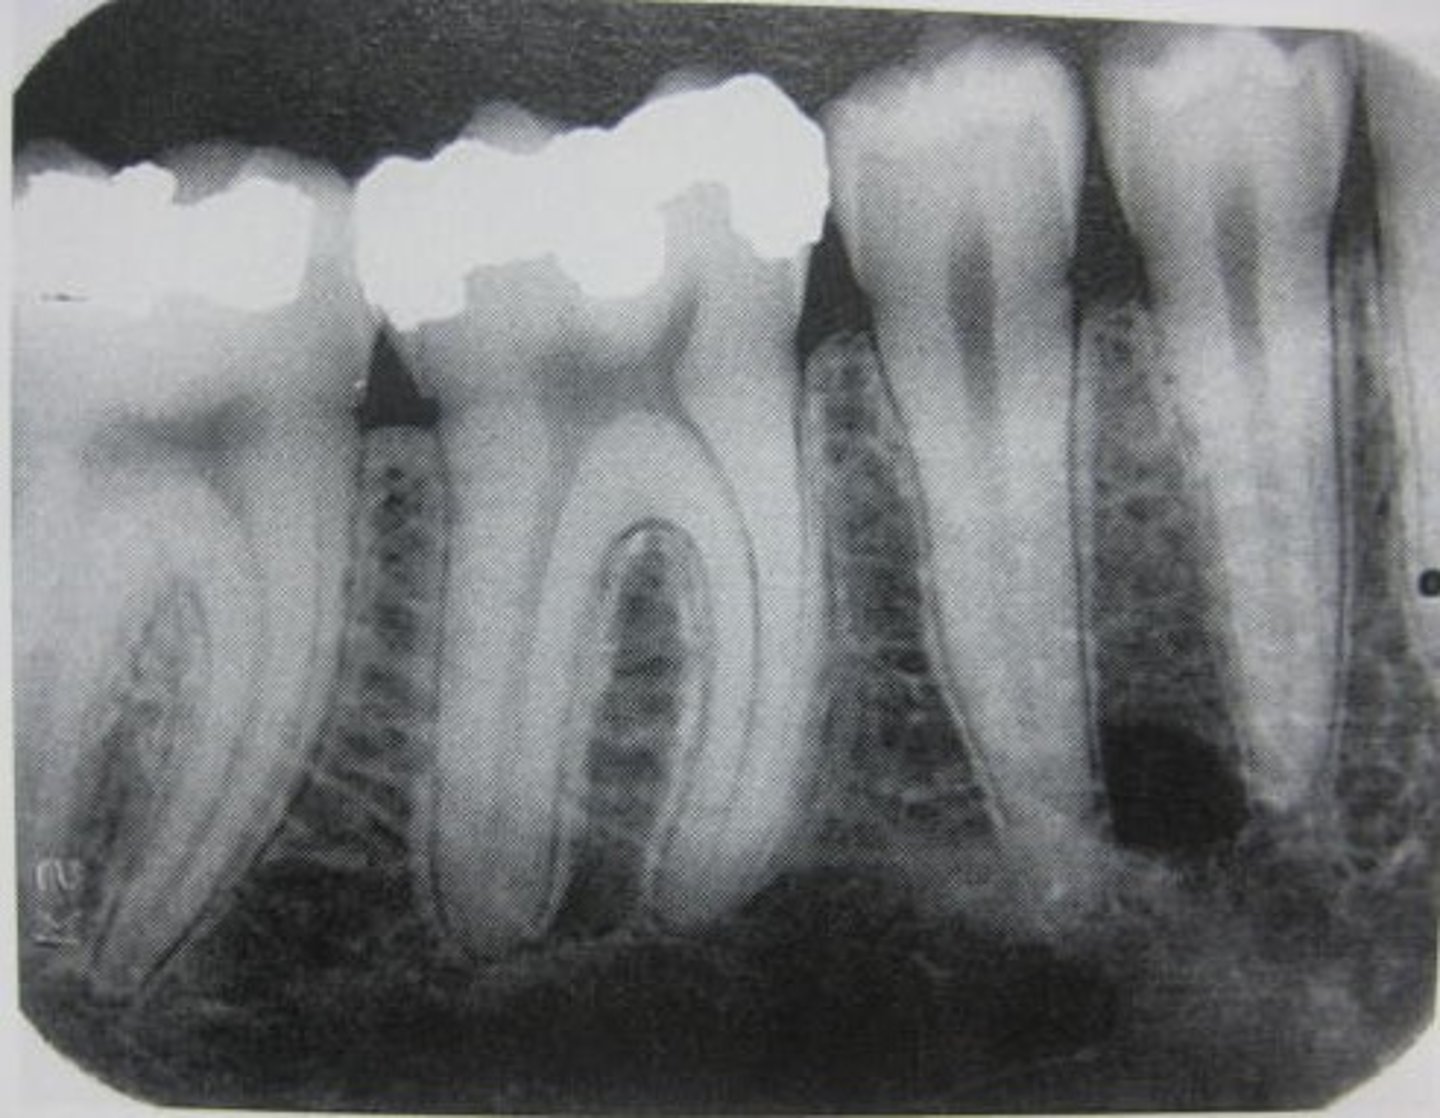

Periapical

what type of x-ray is this?

What does a periapical X-ray show?

the entire tooth from the biting surface (crown) to 2-3mm beyond the root tip (apex)

What is the primary purpose of a periapical x-ray?

DIAGNOSING APICAL PATHOLOGY (aka; abcesses or infections at the root tip)

What are other purposes of a periapical x-ray?

- evaluating root fractures or unusual root anatomy

- used during root canal therapy (Endodontics)

What would be an acceptable PA?

when it shows the entire apex and at least 2-3mm of surrounding bone